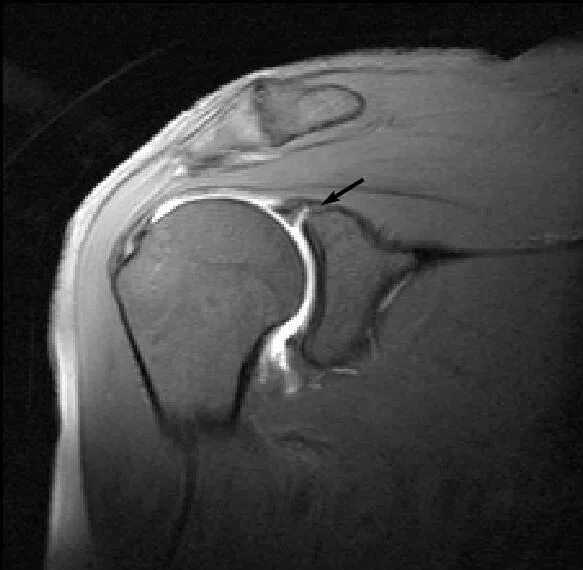

Изменение фиброзной губы гленоида